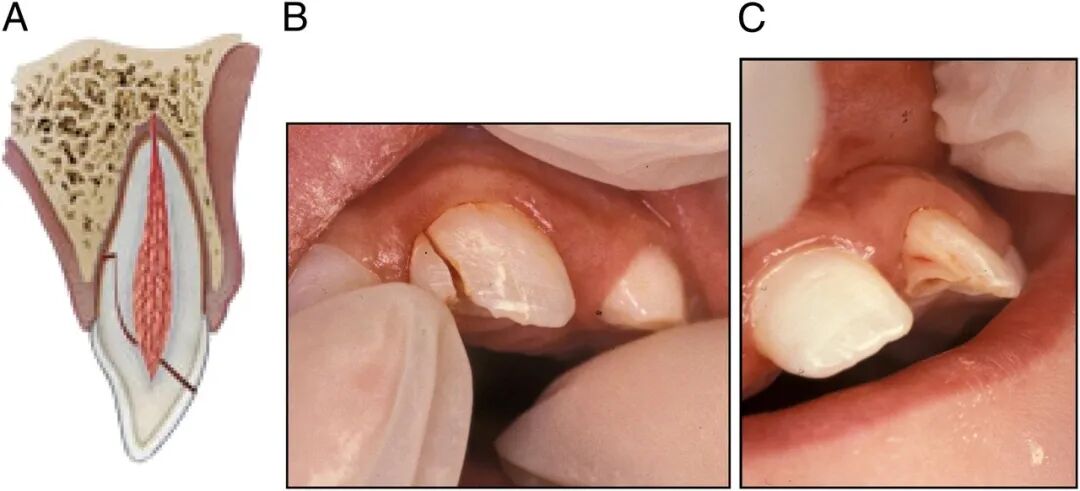

1、牙齿摔“歪”

摔歪的牙齿通常是牙齿尖往里(舌侧方向)歪。

侧脱位

严重的牙齿可能摔“短”一截,甚至摔没了,整颗牙直接“楔”进牙槽骨里。

入侵式脱位

摔歪的牙齿,一般伴有疼痛、松动、出血,同时出现咬合障碍,家长没有什么急救方法,能做的就是尽快就诊。

脱位幅度小的,医生可能会什么都不做,等牙齿自己复位;也可能手动把牙齿复位,然后等它自己长好;严重的,可能上夹板固定,跟处理骨折一样;再严重的,可能直接拔掉。